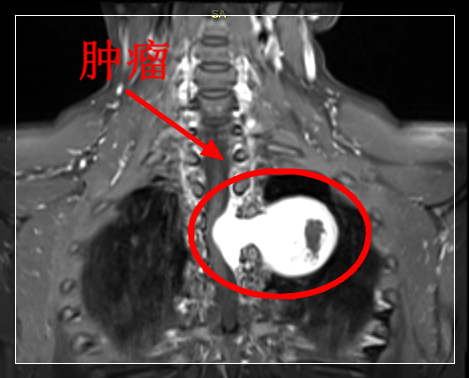

临床上,椎管内神经鞘瘤的诊断多需借助影像学检查,较常用的有椎管造影、腰椎穿刺、脊柱平片、CT及核磁共振(MRI)。其中,MRI是目前最精确的影像学检查方法(肿瘤在MRI T1加权图像上呈髓外低信号瘤灶,在T2加权图像上呈高信号瘤灶;增强扫描:实体性肿瘤呈均匀强化,囊性肿瘤呈环形强化,少数肿瘤呈不均匀强化。另视肿瘤所在解剖层次不同,出现相应的脊髓移位)。

(哑铃状椎管内神经鞘瘤)